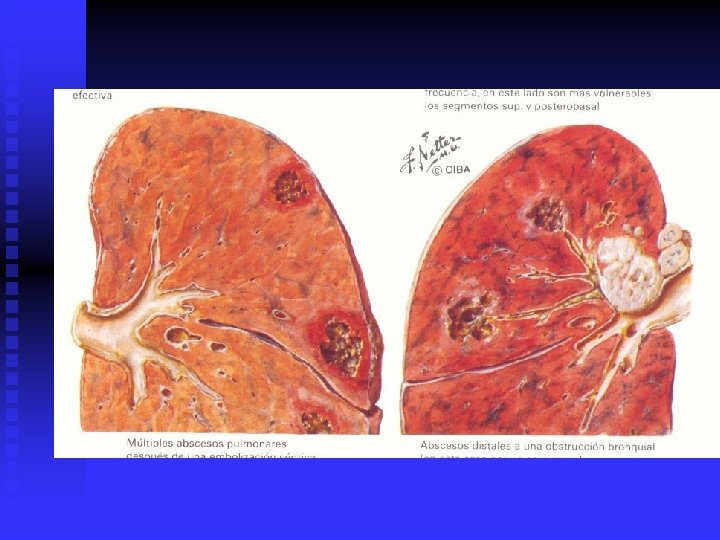

Absceso pulmonar n Infección pulmonar con necrosis en su interior y tendencia a la formación de una pared fibrosa. n Etiología: Gérmenes múltiples n Aerobios Estreptococos Estafilococos Escherichias n n n Anaerobios Fusobacterias Bacteroides Clostridia

Absceso Pulmonar n n n n FACTORES PREDISPONENTES: Niños: Prematurez, malformaciones cardio-pulmonares Ancianos: Cáncer pulmonar, esteroides, diabetes, cirugía, inhaloterapia. MECANISMOS: Aspiración: Inconciencia por convulsiones, alcohol, drogas, reflujo gastroesofágico. Obstrucción: Tumor, cuerpo extraño, secreciones Hematógenos: Drogas IV, infarto pulmonar, sepsis abdominal.

Absceso Pulmonar n DIAGNÓSTICO. n CLINICO. Neumonía, septicemia RADIOLOGICO. Rx. PA y lateral, TAC. BACTERIOLOGICO: Frotis Gram. Cultivos ENDOSCÓPICO O PUNCIÓN n n n n TRATAMIENTO. Antibióticos múltiples. 6 a 8 semanas Inhaloterapia y Fisioterapia del tórax Broncoscopía para drenaje Drenaje quirúrgico y resección